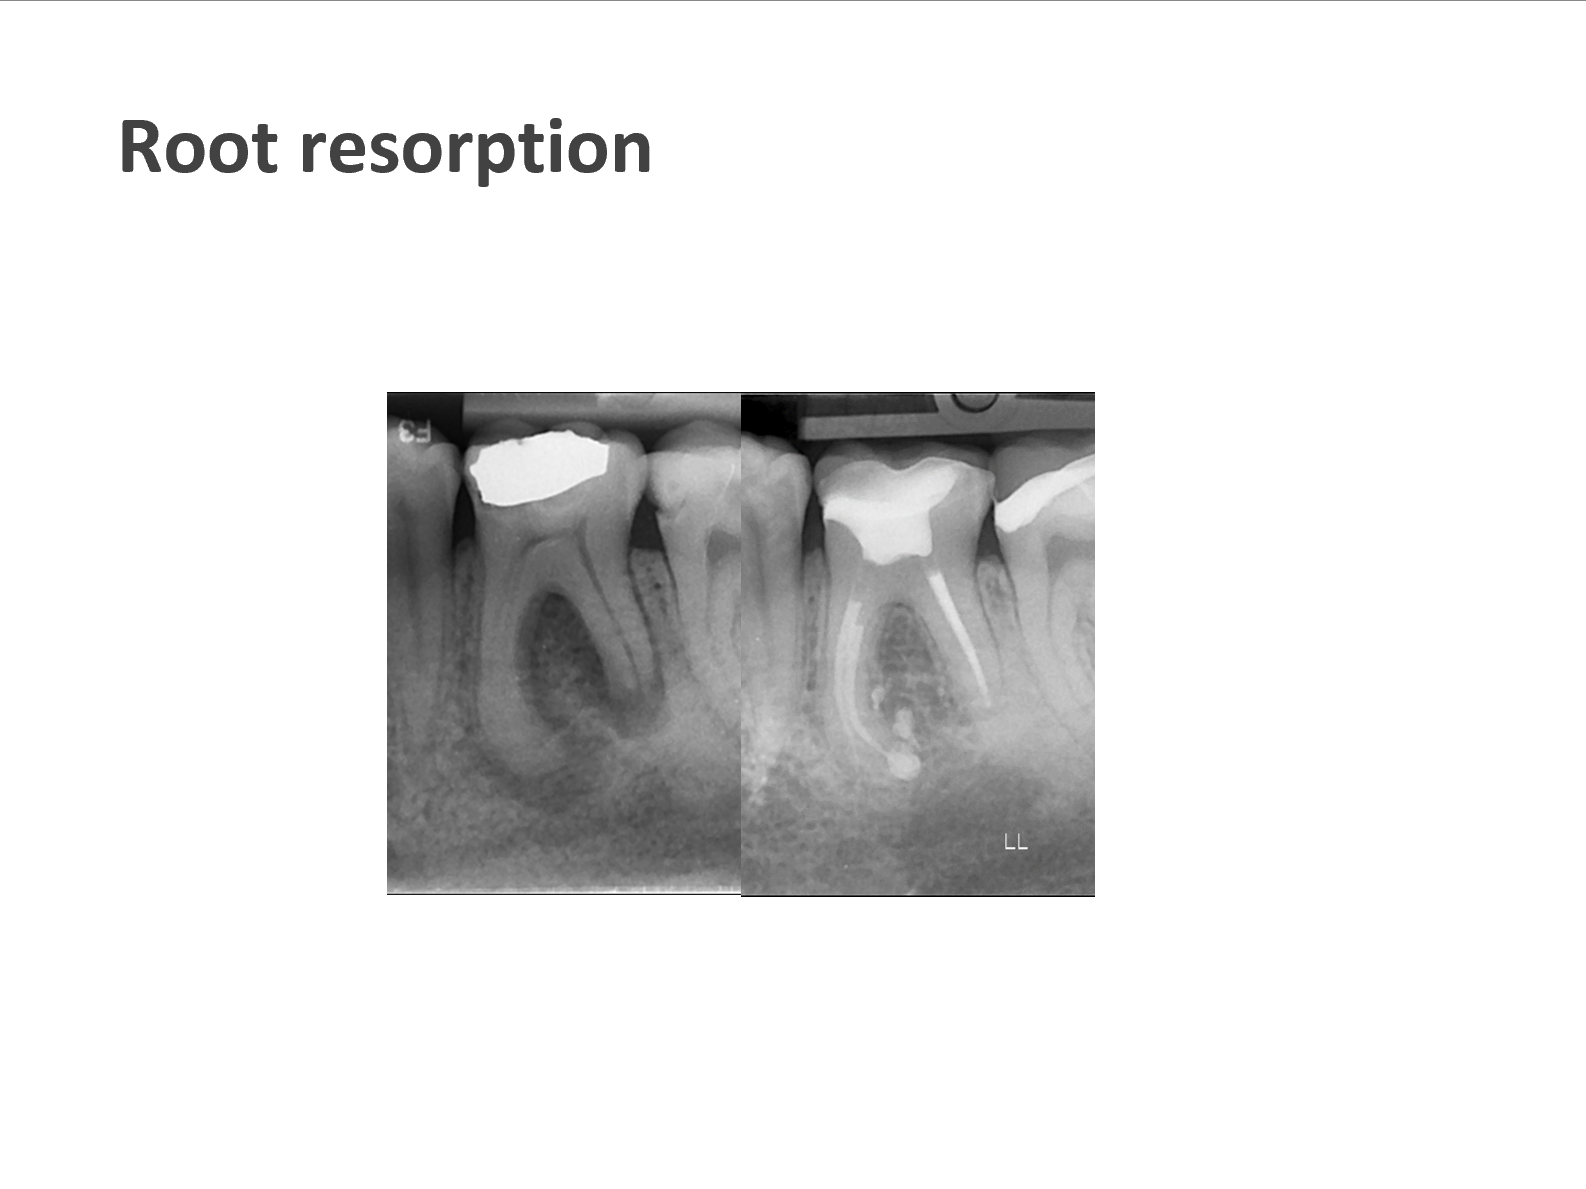

We take pride in providing the highest standard of care at ICE and believe that only the best is good enough for our patients. As such, Shakil completes all endodontic procedures using a state-of-the-art dental microscope. We accept referrals for consultations, root canal treatment (primary and retreatment), management of endodontic emergencies, dentoalveolar trauma and we are also happy to provide definitive restorations as required.